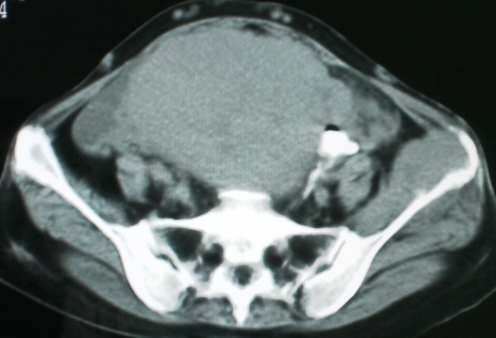

以下是引用zsl6918在2008-11-4 19:14:00的发言:[br]多发转移性改变,子宫改变不除外为原发灶